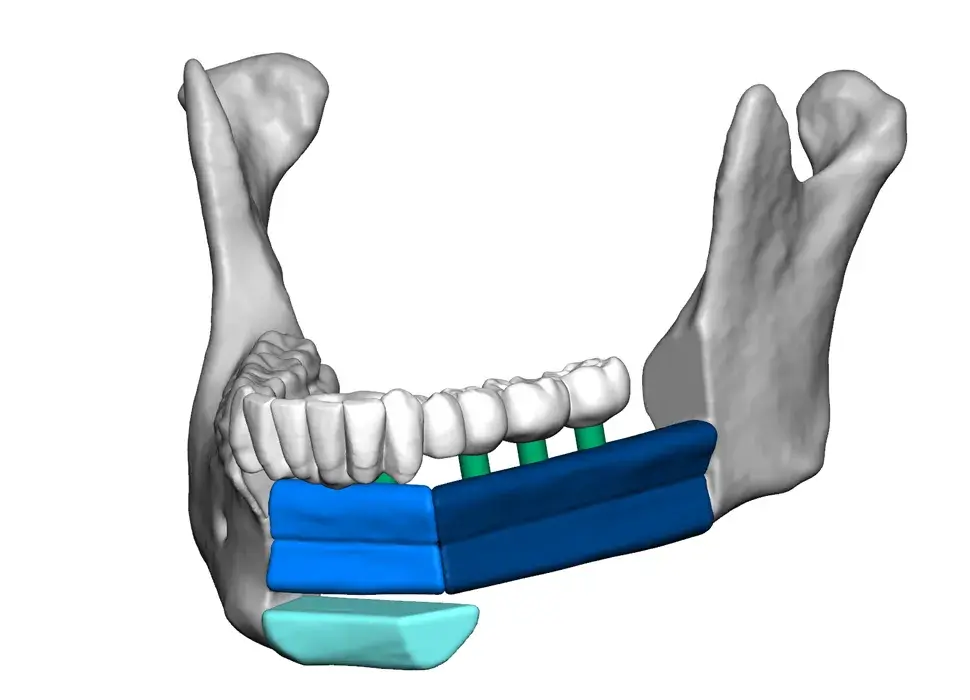

3D Systems' VSP® surgical planning solutions for craniomaxillofacial (CMF) applications received FDA clearance as a service-based approach to personalized surgery over 10 years ago.

3D Systems and Stryker Corporation have partnered to provide surgeons with best-in-class products and services for craniomaxillofacial surgeries. As a leader in personalized healthcare solutions, 3D Systems has planned and delivered devices for more than 140,000 patient-specific cases. The Stryker Craniomaxillofacial business specializes in providing patient-specific options and innovative solutions that help drive efficiencies in surgical suites. The combination of Stryker’s specialized team and advanced implants with 3D Systems' cutting-edge 3D printing technologies and expert consulting services positions both companies to provide a superior level of service to healthcare professionals who use these revolutionary solutions.